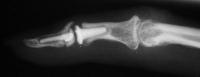

The trial implant sizer shows the true size of the implant. The final implant has a radiolucent coating  which makes it appear smaller than it is on Xray.

Final implant radiographs.

The final implant: